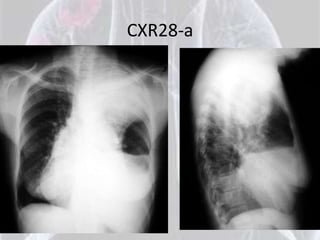

CXR28-a

CXR28-b

Old film

CXR28:

Aneurysm Arch of Aorta

Leaking Blood into Pleural Space

• Mediastinal mass

• Calcification of periphery evident along upper margin

• Loss of silhouettes of

– aortic knob

– left heart margin

– left diaphragm

• Left pleural effusion

• Tracheal indentation

• Lateral view

• Middle mediastinal mass

• Calcification of periphery in lateral view

• left diaphragm not visible due to fluid in pleural space